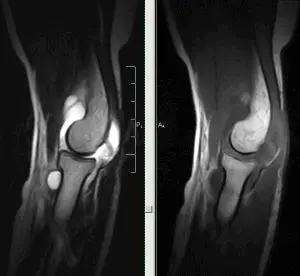

На МРТ-изображении: синовит локтевого сустава.